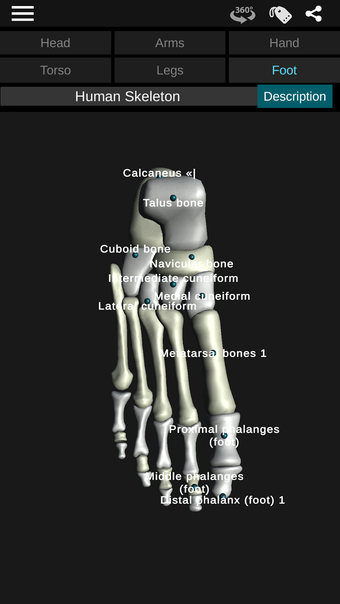

Through a series of educational exercises, users can learn to identify different bones and the location of each in the body.

By selecting one of the bones in the model, users can explore its form, location, and identification. In addition, users can move, rotate, and zoom the model to better understand its shape and location in the body. There are descriptions of different bones in the body, such as the skull, jaw, scapula, femur, tibia, pelvis, humerus, sternum, and vertebrae.